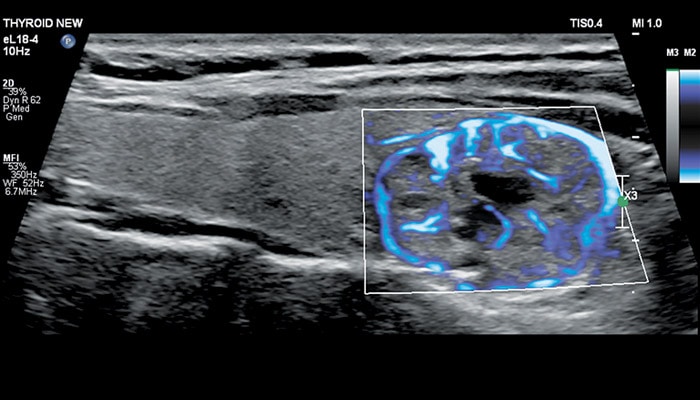

Визуализация кровотока

Philips Microflow Imaging

Линейный матричный датчик eL18-4 поддерживает режим высокочувствительной визуализации кровотока (Philips MicroFlow Imaging), новый запатентованный метод, который обеспечивает инновационный подход к оценке сосудистого русла. Визуализация MicroFlow преодолевает многие барьеры, связанные с традиционными методами обнаружения кровотока в малых сосудах, обеспечивая высокое разрешение при минимальных артефактах.

Метод MicroFlow Imaging поддерживает высокую частоту кадров и качество изображения, применяет инновационные методы сокращения артефактов. Варианты вычитания 2D-изображений, смешивания и параллельного отображения обеспечивают превосходную визуализацию в различных клинических случаях.